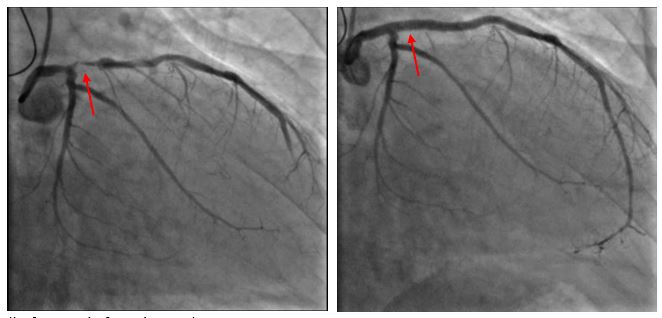

(before and after pictures)